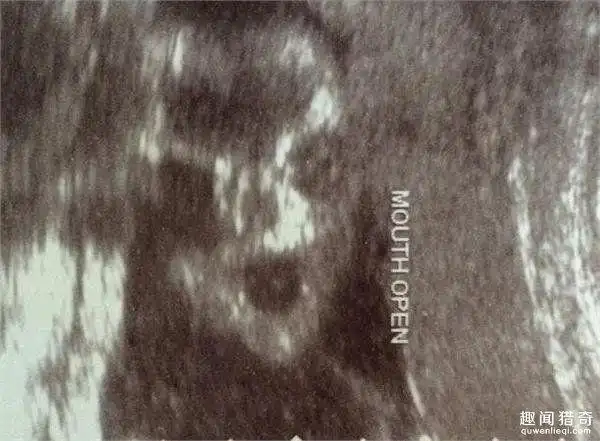

准妈妈去体检,看到b超下的婴儿差点吓哭!